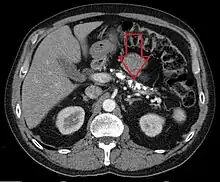

Axial CT showing multiple calcifications in the pancreas in a patient with chronic pancreatitis | |

Computed tomography, magnetic resonance cholangiopancreatography (MRCP), and endoscopic ultrasound (EUS) all have similar sensitivity and specificity for diagnosing chronic pancreatitis.[4] MRCP is particularly utilized for its sensitivity in imaging the pancreatic ducts and bile ducts for associated changes such as stones or strictures.[4][12] A biopsy of the pancreas is not required for the diagnosis.[4] On imaging, pancreatic and bile duct dilatation, atrophy of the pancreas, multiple calcifications of the pancreas, and enlargement of pancreatic glands can be found.[12]